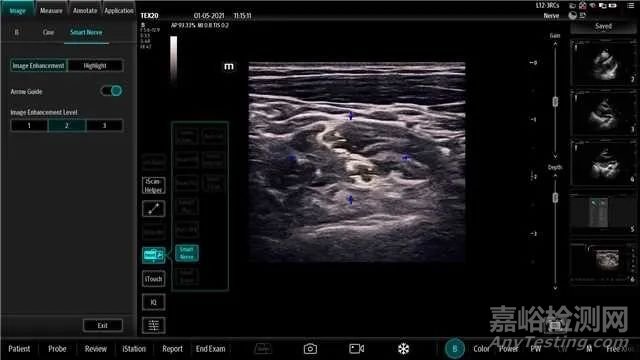

圖3 神經(jīng)自動識別功能開啟后操作界面

神經(jīng)自動識別功能軟件采用深度學習技術,可通過增強臂叢神經(jīng)區(qū)域圖像,使得臂叢神經(jīng)區(qū)域更容易辨識。在臨床使用中,神經(jīng)自動識別功能可以用于輔助正常臂叢神經(jīng)的超聲影像學觀察以及神經(jīng)阻滯前的定位。

操作者按照說明書規(guī)范的操作流程,選擇線陣探頭及神經(jīng)檢查模式,在B模式下沿病人肌間溝或鎖骨上區(qū)域行走掃查,在達到目標解剖區(qū)域后啟動神經(jīng)自動識別功能,可得到增強的臂叢神經(jīng)區(qū)域圖像,以便更容易辨識臂叢神經(jīng)形態(tài)特征,最終結果需要由醫(yī)生基于專業(yè)知識確認以及修改。